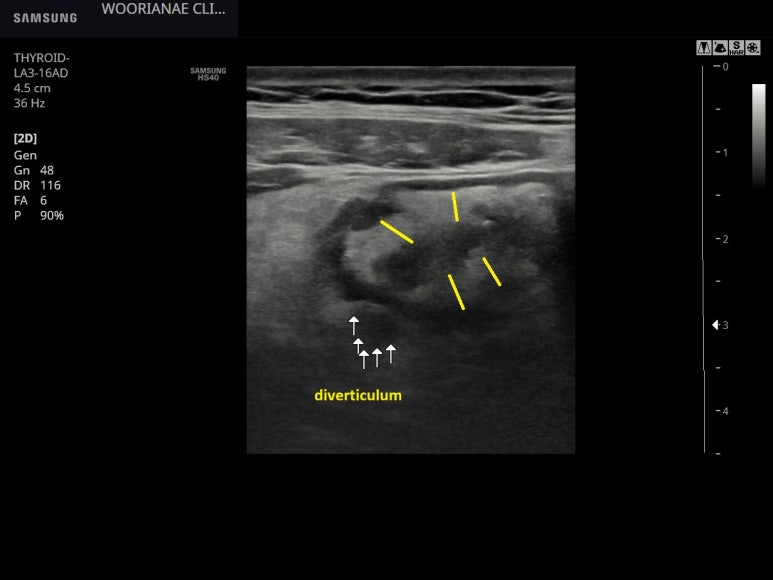

https://blog.naver.com/ejercicio/221636509611 그물울혈반에 더해 청피반성 혈관염 증상? 반복.. : 네이버블로그 상기 환자 21년도에 갑상선 전절제 시행 23년에는 반복적으로 혈압이 높아 CCB를 반알만...